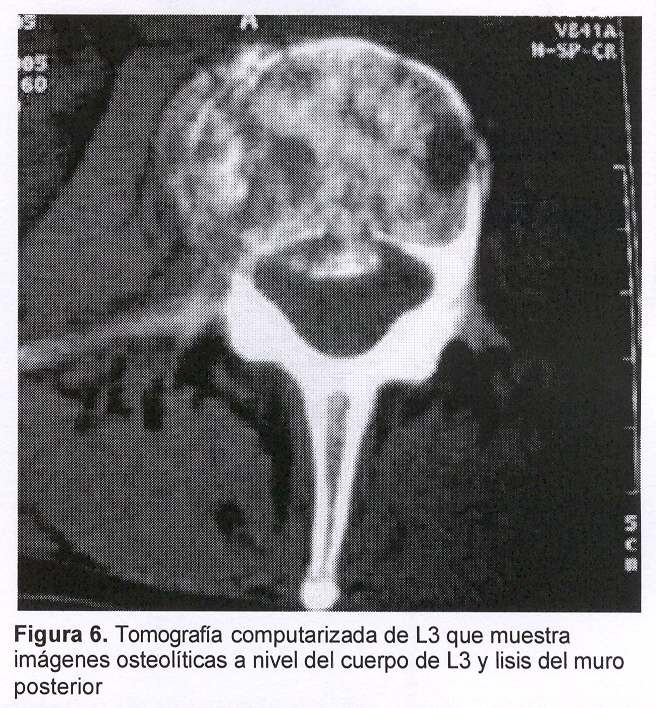

Sexo femenino, 43 años, con cuadro de 45 días de evolución dado por dolor raquídeo lumbar intenso, de comienzo súbito y evolución progresiva a pesar del tratamiento médico. Al igual que en el caso anterior el dolor era tan intenso que la obligaba a mantener reposo absoluto en cama. Al examen físico presentaba intenso dolor raquídeo a la palpación de L3, sin signología radicular ni deficitaria. Fue estudiada con radiografía simple (figura 5) y TC de columna lumbosacra que mostraban: aplastamiento del cuerpo vertebral de L3 a predominio de la plataforma inferior y falta de definición del pedículo derecho, múltiples imágenes líticas a nivel del cuerpo y del pedículo derecho con lisis parcial del muro posterior, abombamiento hacia el canal raquídeo (figura 6). Existían, además, otras imágenes líticas a nivel costal a la altura de la undécima costilla derecha. Las imágenes correspondían a sustitución ósea por metástasis. En esta paciente no existía noción de tumor primitivo por lo cual se planteó la realización de biopsia de la lesión concomitantemente con el tratamiento mediante vertebroplastia percutánea (figuras 7 y 8).